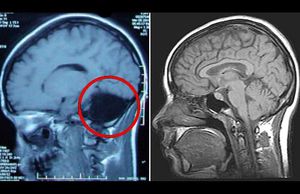

A 15yr child born without cerebellum as shown in the MRI. Having a history of balance problem during walking running or any daily activities. Strange right.?

Breathing is compensated by other centers of the brain however patients with this condition always have a certain level of clumsiness. This can be slightly moderated by training in sports. The only other case I've ever seen was in a 26 yr old female.